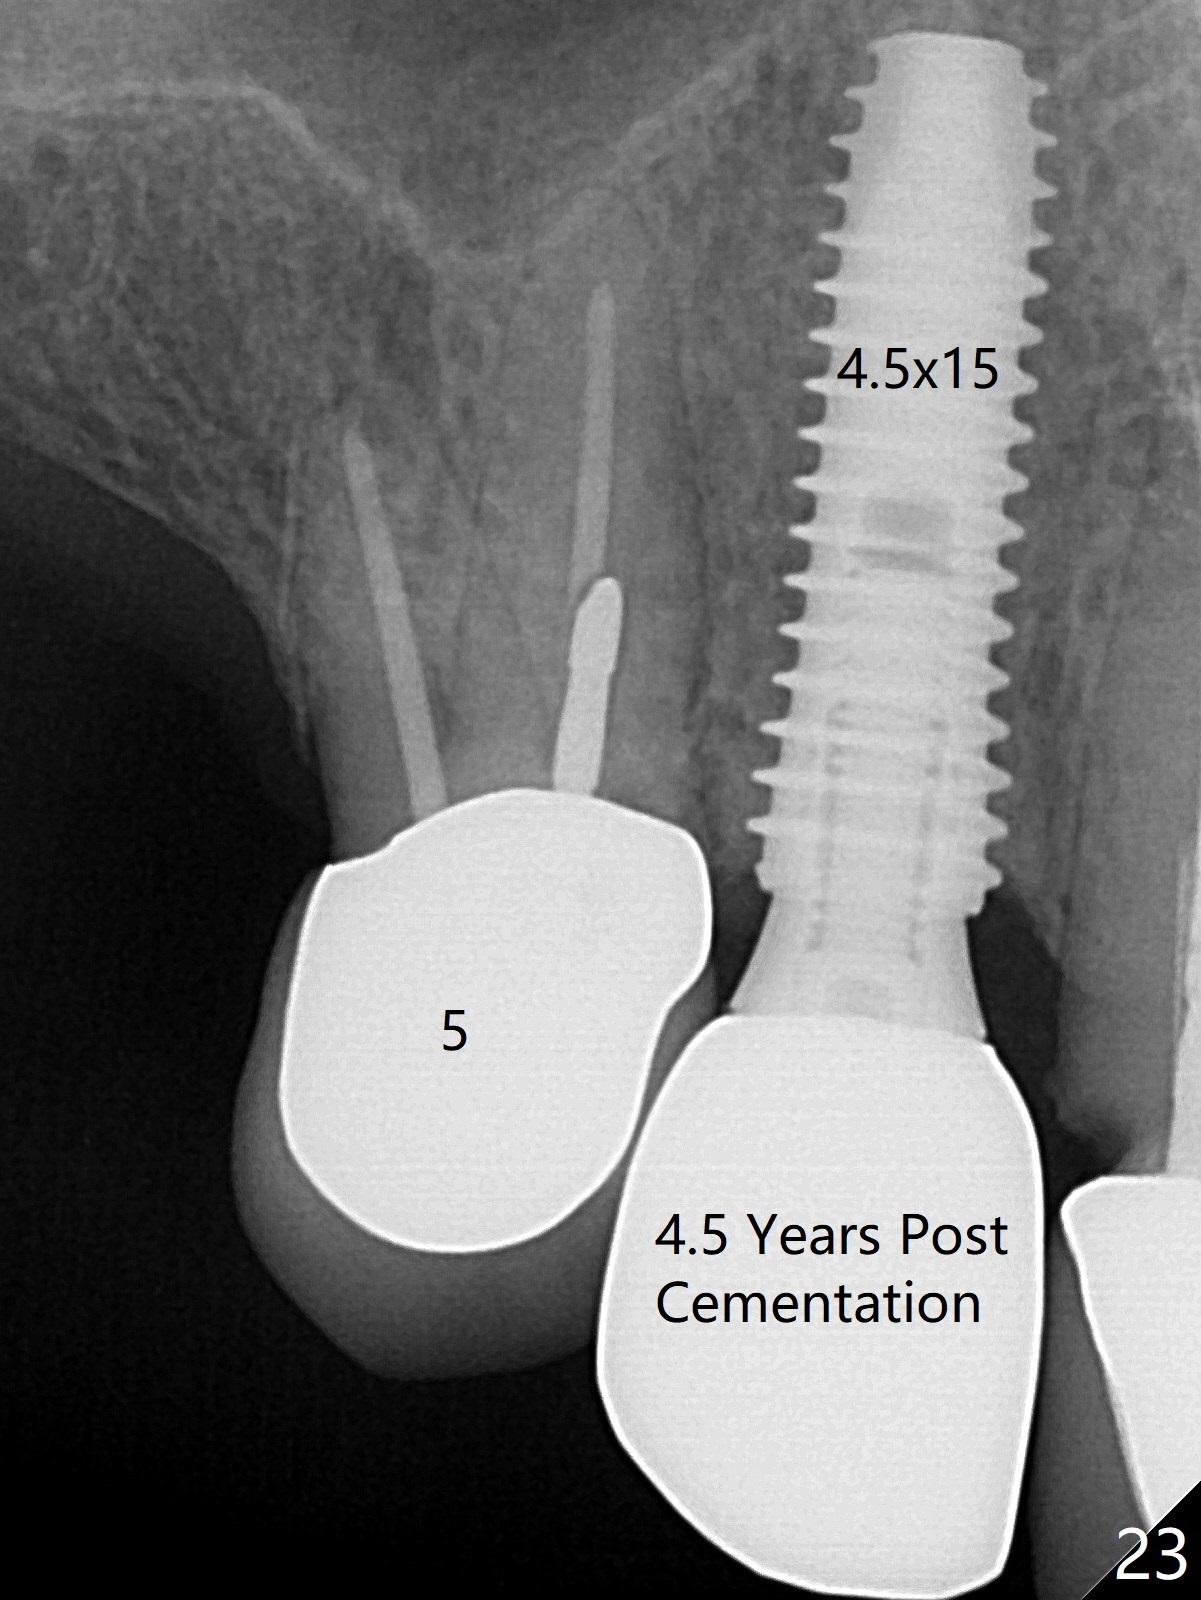

Six months post cementation, the tooth #9 becomes symptomatic.  Is it possible that the implant at #10 is too close to the root of #9?  It is asymptomatic after pulpotomy, but the tooth fractures equi/supragingivally.  Two PAs taken while RCT show osteointegration at #10-12 (Fig.18,19).  While the bone density increases at #10 regular implant, there is minimal bone loss around the 1-piece implants 13 months post cementation (18 months postop, Fig.20,21).  The gingiva remains healthy 19 months post cementation (Fig.22).  76岁病人突然打电话说一个植牙牙冠松动,其实9号牙(自然牙)折裂,6,10-13号牙植牙好像没有骨质吸收(图二十三至二十五),10-13牙位牙龈健康(图二十六,行使功能五年)。9号牙牙冠重新粘固后,显示前牙深覆合,深覆盖(图二十七,二十八)。如果再次脱落需要植牙,选择一段式有助于植入和修复,因为植体和基台直径小。两段式植牙相对基台直径至少4,或者4.5毫米,前牙修复显得笨重。由于9,10牙根和植体接近,9号牙植体需要偏小而长,3x14或者15毫米(图二十九)。